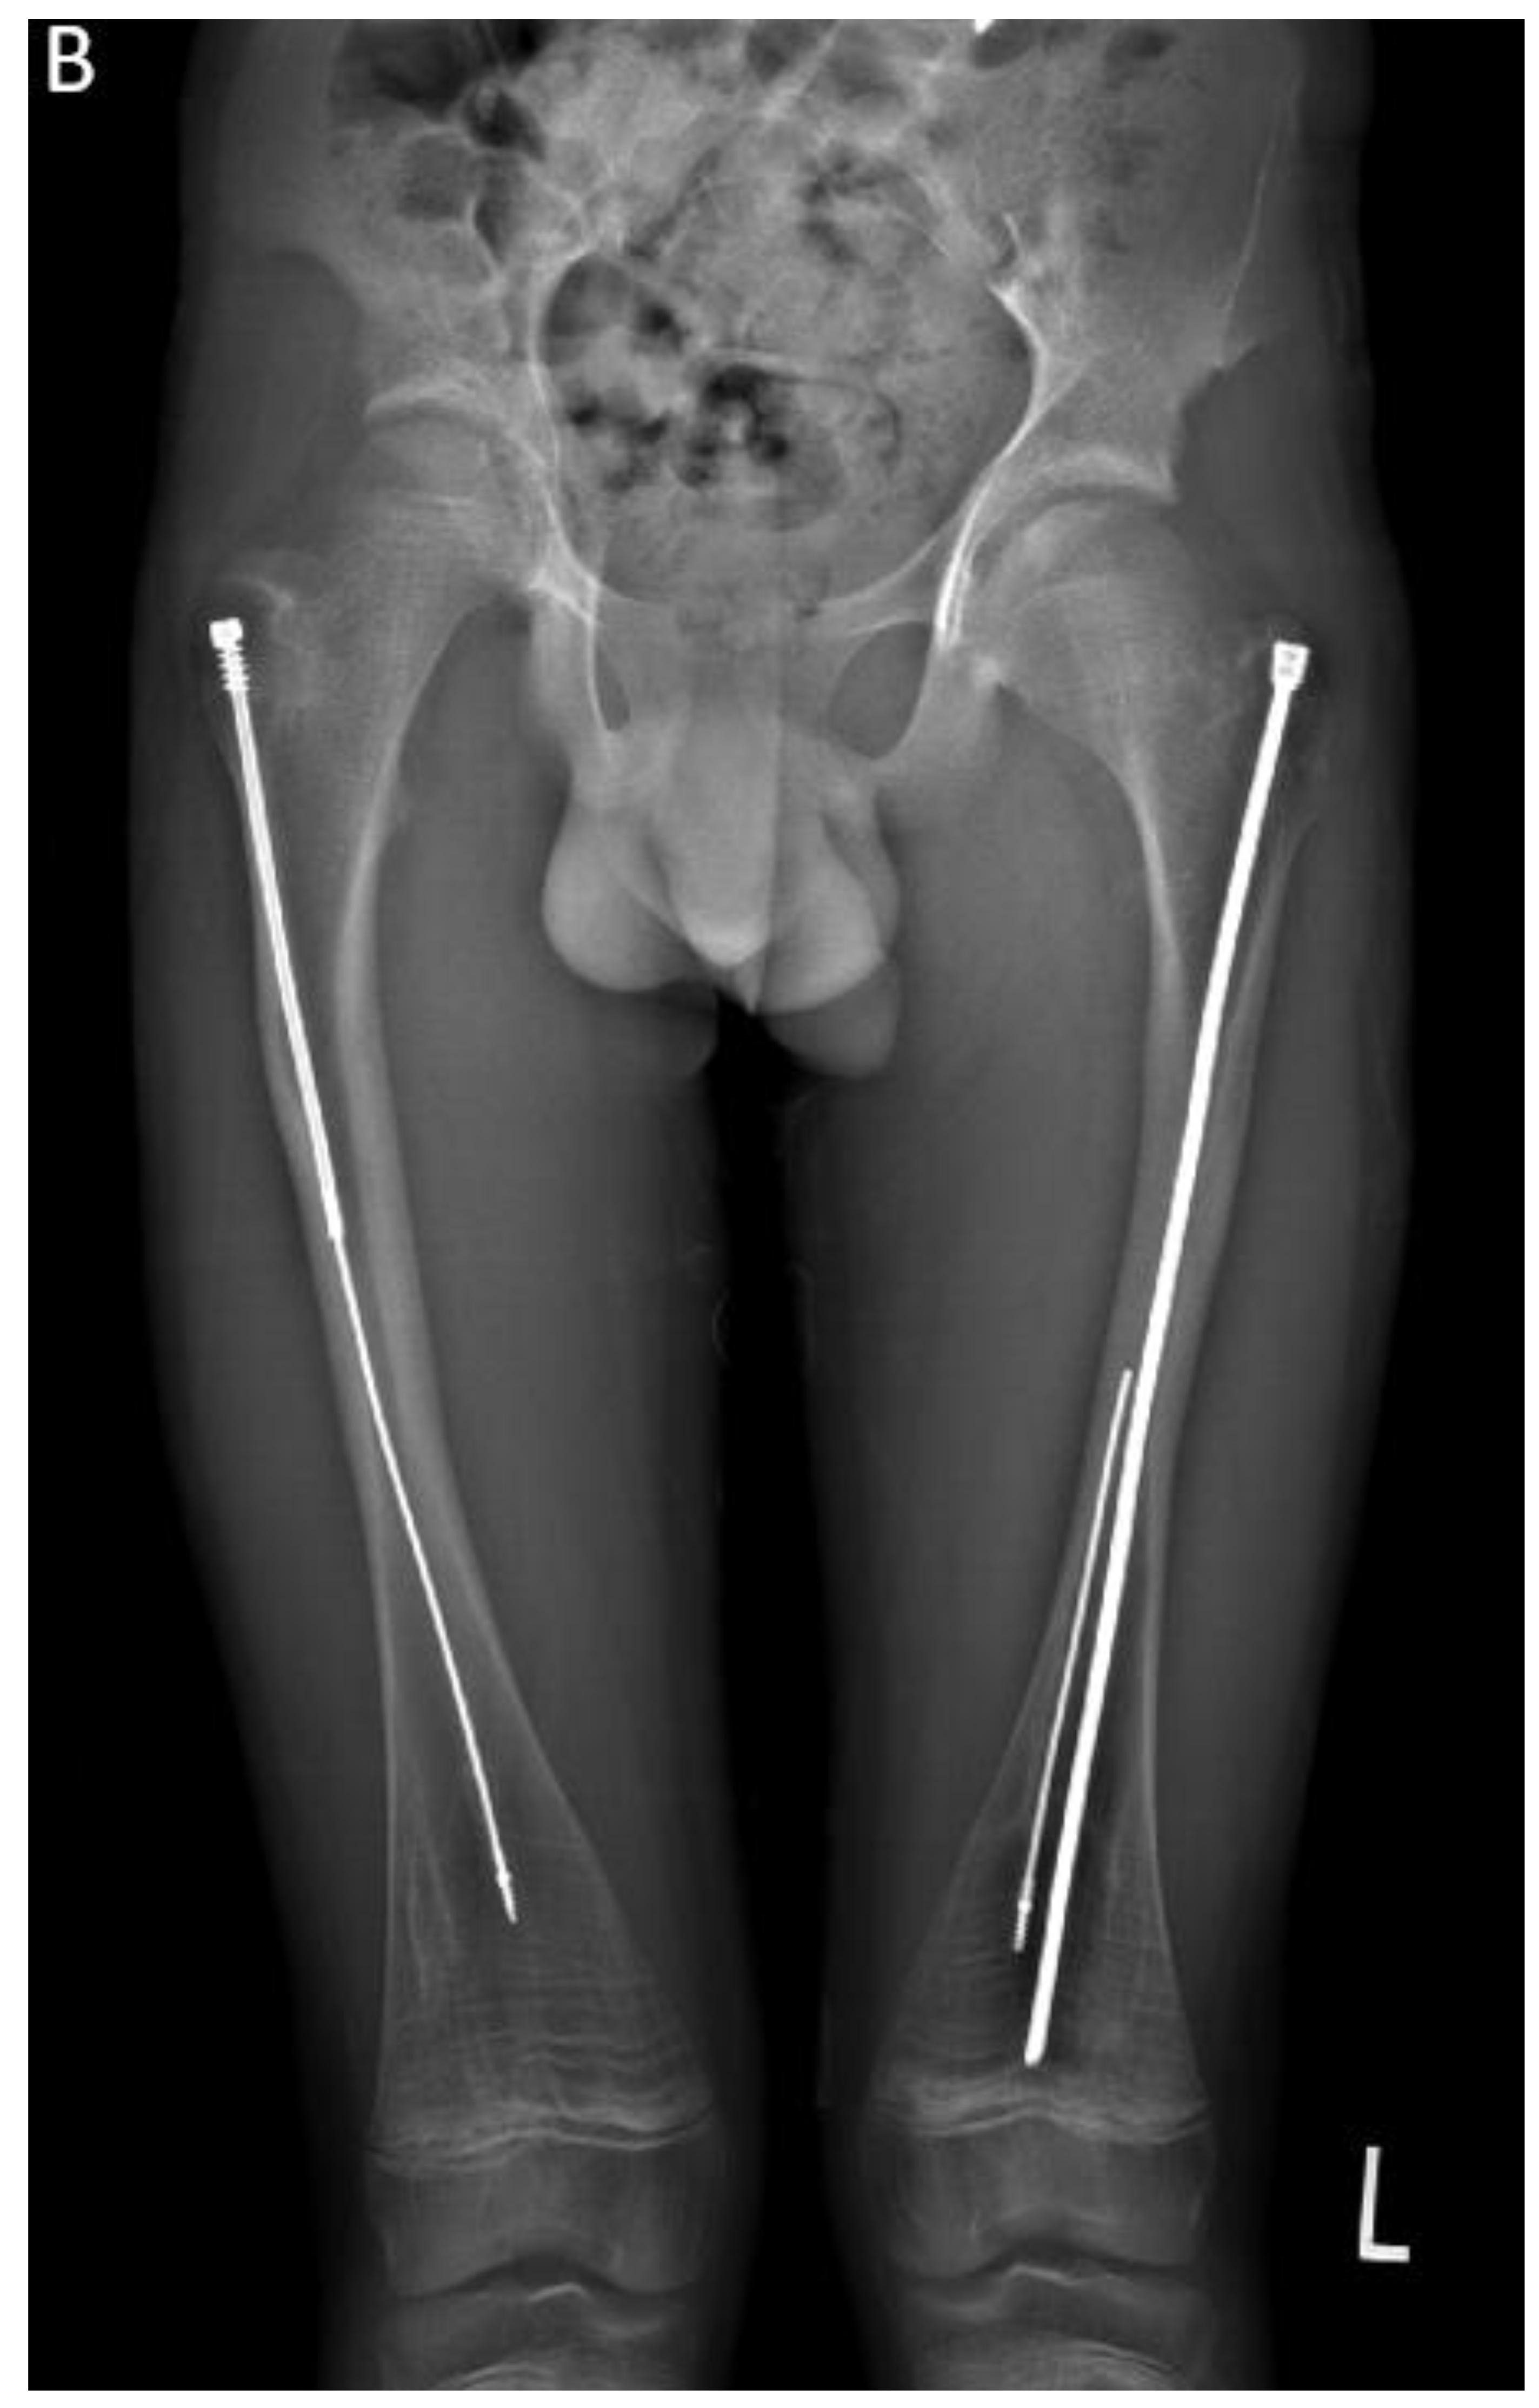

In the second case presented in this paper, a 15-year-old boy diagnosed with OI type IV, who was previously operated on 12 years ago with bilateral FD rods, presented to his regular clinic visit with pain over the left greater trochanter. This patient was ambulating without any braces or aids and was functioning very well. He did not sustain any fractures since the FD rod insertion, and full ROM of his hips was maintained. X-ray showed a completely disengaged FD rod on the left side, where the female component migrated distally and laterally across the lateral cortex. The protruding proximal part of the female component was the site of the pain and tenderness (Figure 10A). On the right side, the FD rod was almost disengaged, and a mild deformity was present anterolaterally. The X-ray demonstrates that the intramedullary canal is too narrow to accommodate an adult-sized nail. As the patient had almost reached skeletal maturity, it was decided not to use another telescoping rod but instead to use a non-telescoping SLIM nail. Because the distal male component of the existing Fassier Duval rod was situated deep into the canal, making its retrieval problematic, it was decided pre-operatively to leave it in situ and insert the new rod beside it. The female component on the left side needed to be removed, and a solid SLIM rod was inserted to protect the bone (Figure 10B). Revision to a non-telescoping rod was considered for the right side as well, however, surveillance was opted for as the patient was approaching skeletal maturity. In this case, the indication for use of the SLIM nail is a near skeletally mature patient, therefore, not requiring a telescoping nail. However, the intramedullary canal was too narrow to accommodate a larger solid nail.

Figure 10. A - Pre-operative X-ray. B- Post-revision X-ray showing installed SLIM nail in the left femur.